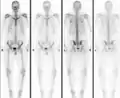

مسح عظمي طبيعي في شخص مصاب بتبكل العظام